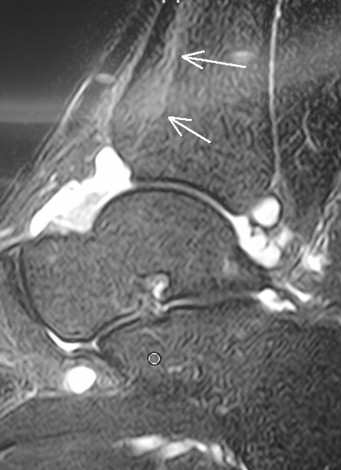

右圖的磁力共振顯示這名年輕人的脛骨下端有骨折(白色箭嘴),血液經骨折滲進踝關節(白色的地方)